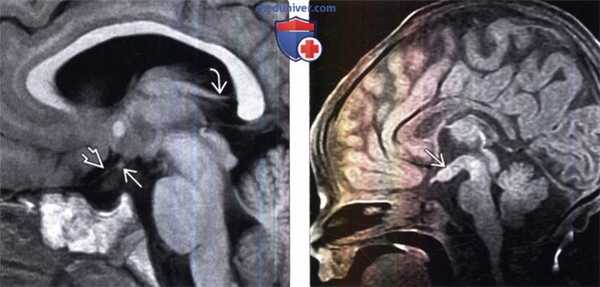

(Слева) МРТ, Т2-ВИ, корональный срез: у новорожденного с расщелиной основания черепа по срединной линии выявляются две воронки гипофиза, имеющие нормальные размеры и проходящие от зрительного перекреста к гипофизам.

(Справа) МРТ, Т1 -ВИ, корональный срез: визуализируются два гипофиза нормальных размеров, смещенные латерально и расположенные в основании черепа аномального строения. Гипофизы имеют однородный гиперинтенсивный сигнал вследствие влияния гормонов матери. В норме у новорожденных на Т1-ВИ гипофиз имеет диффузно гиперинтенсивный сигнал.

(Слева) На рисунке сагиттальною среза показана классическая гамартома серого бугра на ножке, расположенная между воронкой спереди и сосцевидными телами сзади. Данное объемное образование схоже с серым веществом.

(Справа) МРТ, Т1-ВИ, сагиттальный срез: у восьмилетней девочки с преждевременным половым созреванием визуализируется классическая гамартома гипоталамуса на ножке по типу «запонки». Это образование расположено между воронкой гипофиза спереди и сосцевидными телами сзади. Классическая гамартома гипоталамуса (ГГ) имеет изоинтенсивный сигнал по отношению к серому веществу. (Слева) МРТ, Т2-ВИ, сагиттальный срез: у пациента с преждевременным половым созреванием определяется объемное образование гипоталамуса на ножке, расположенное между срединным возвышением и сосцевидными телами. Данное образование имеет изоинтенсивный по отношению к коре сигнал.

(Справа) МРТ, постконтрастное Т1 -ВИ, сагиттальный срез: у этого же пациента отмечается отсутствие накопления контраста объемным образованием. Это классический случай гамартомы гипоталамуса (ГГ) на ножке.